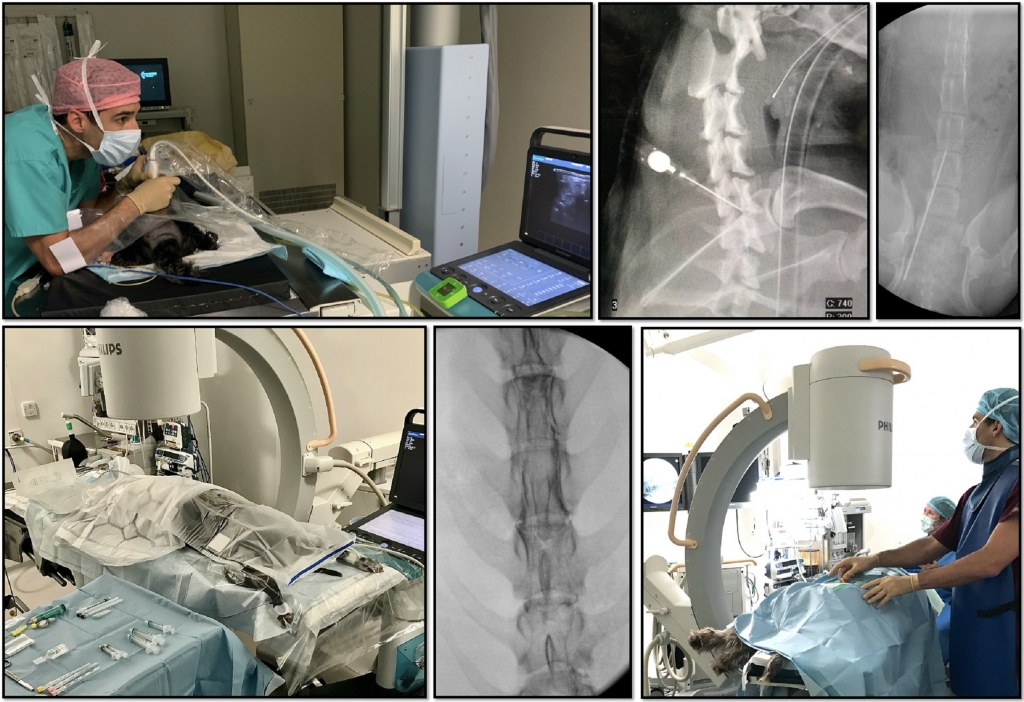

He said: “Interventional pain management, or interventional analgesia, involves a wide range of image-guided injections, using ultrasound and fluoroscopy in the process, with the aim of treating and helping to understand acute and chronic pain management and improving the quality of life of the patient.

The service, which will largely see patients treated and sent home during the same day, will include spinal interventions and interfascial, perineural and intraarticular injections.

He added: “This type of treatment is also beneficial for tackling spinal pain after compression of spinal nerves, as well as pain secondary to radiculopathies, myelopathies, facet joint degeneration and even discopathic pain.